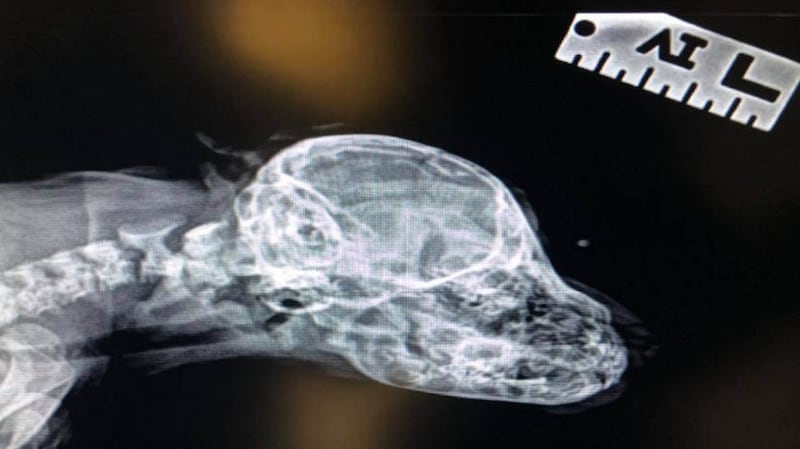

Narwhal visited the vet on Tuesday where X-rays showed there were no bones in the “tail”, which does not wag, and he was given a clean bill of health.

“Everybody has said that it looks like a tail that just didn’t develop fully, like he might have tried to absorb a twin and it just didn’t work all the way,” she said.

“It kind of curls right down under his eyes. We deal with such unique animals here that we love to let them keep their uniqueness.”